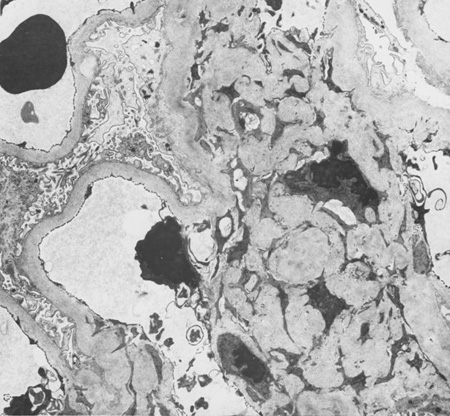

Doença renal diabética

Doença renal diabética: expansão mesangial decorrente do aumento da matriz mesangial e da redução da degradação do colágeno glicosilado

Do acervo do Dr. Raoul Fresco; usado com permissão